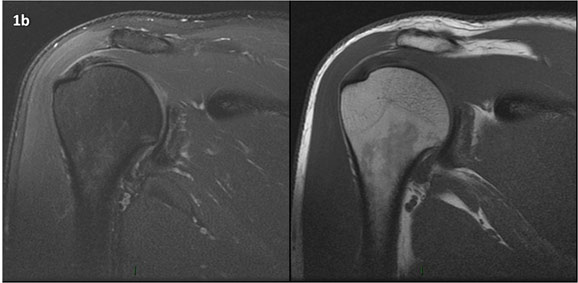

Figura 1 (a-g): Imagens consecutivas de RM no plano coronal nas ponderações DP com supressão de gordura (DP SG) à esquerda e T1 à direita. Clique na seta para passar as imagens.

Figura 1a’ mostrando rotura parcial articular na inserção do supraespinhal (setas azuis).

Figuras 1b’ a 1g’ mostrando atrofia da porção superior do músculo redondo menor (seta salmão), com lipossubstituição mais evidente das mais fibras laterais (seta amarela). As fibras mais inferiores e mediais têm atrofia menos evidente.

Repare que estas alterações não são evidentes nas imagens com supressão de gordura.